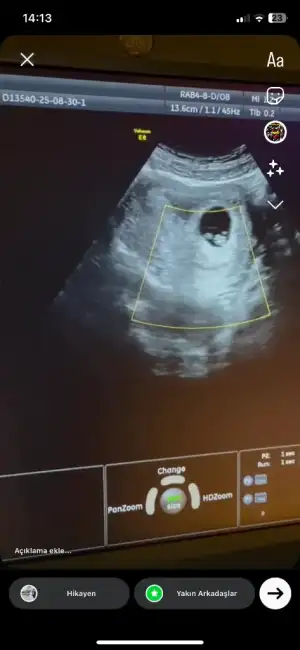

6 haftalik karından ultrasyon tahminde bulunabilir misiniz

• IMG_20250312_112835.webp

IMG_20250312_112835.webp

31,3 KB · Görüntüleme: 70